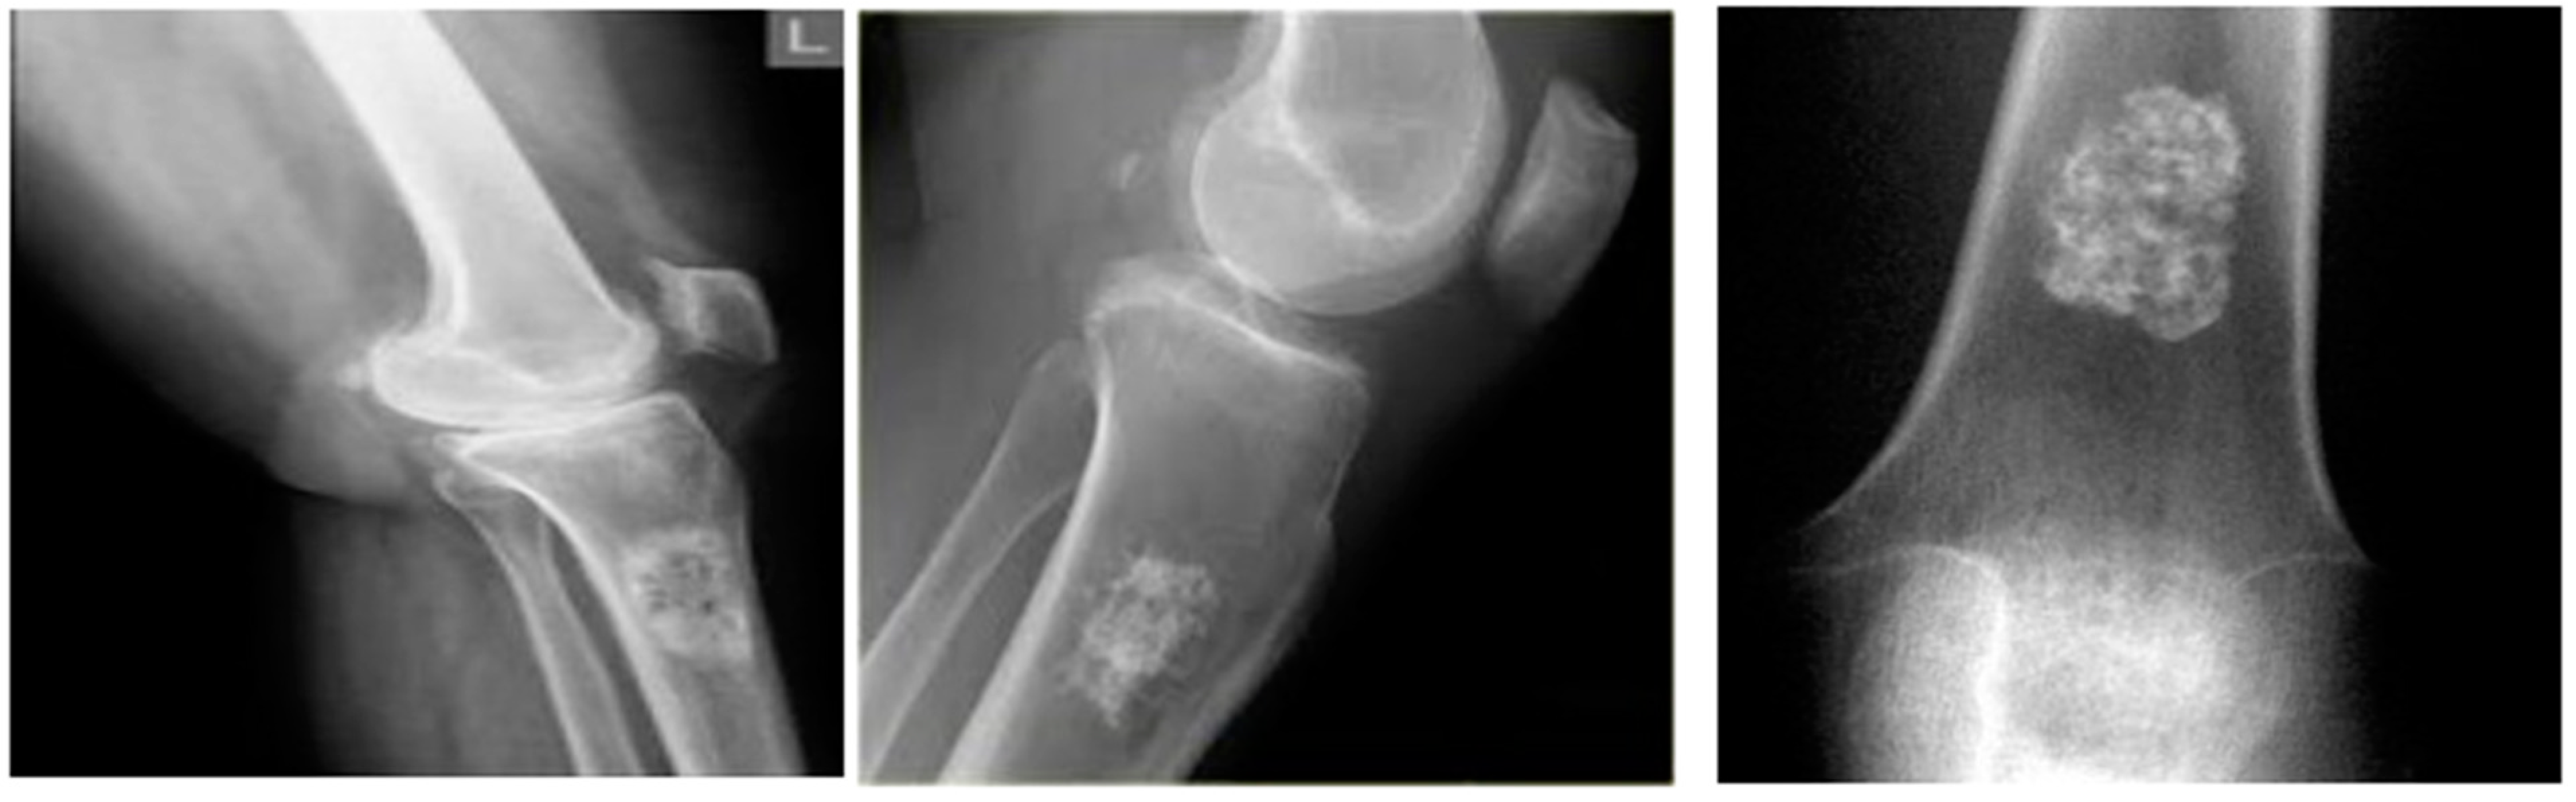

The proposed DTBV system is implemented using bone cancer. X-ray image dataset acquired from the repository of the Indian Institute of Engineering Science and Technology, Shibpur (IIEST) [20], on Google Colab with approximately 13 GB of RAM and 110 GB of disk space. The Google Colab environment is further equipped with a high-performance NVIDIA Tesla K80 GPU. The input dataset contains 100 images, 50 of which are healthy bone images and 50 of which are malignant bone images. The input images are resized to 255 × 255 pixels to establish the base size and uniformity [29]. Figure 2 and Figure 3 show the sample images of healthy and malignant bones. The OpenCV library is used to implement the median filter. The PyTorch library is used to implement the VGG16 model for feature extraction. The sklearn library is used to perform feature selection and to implement the SVM model for classification.

Figure 2.

Healthy bones.

Figure 3.

Malignant bones.